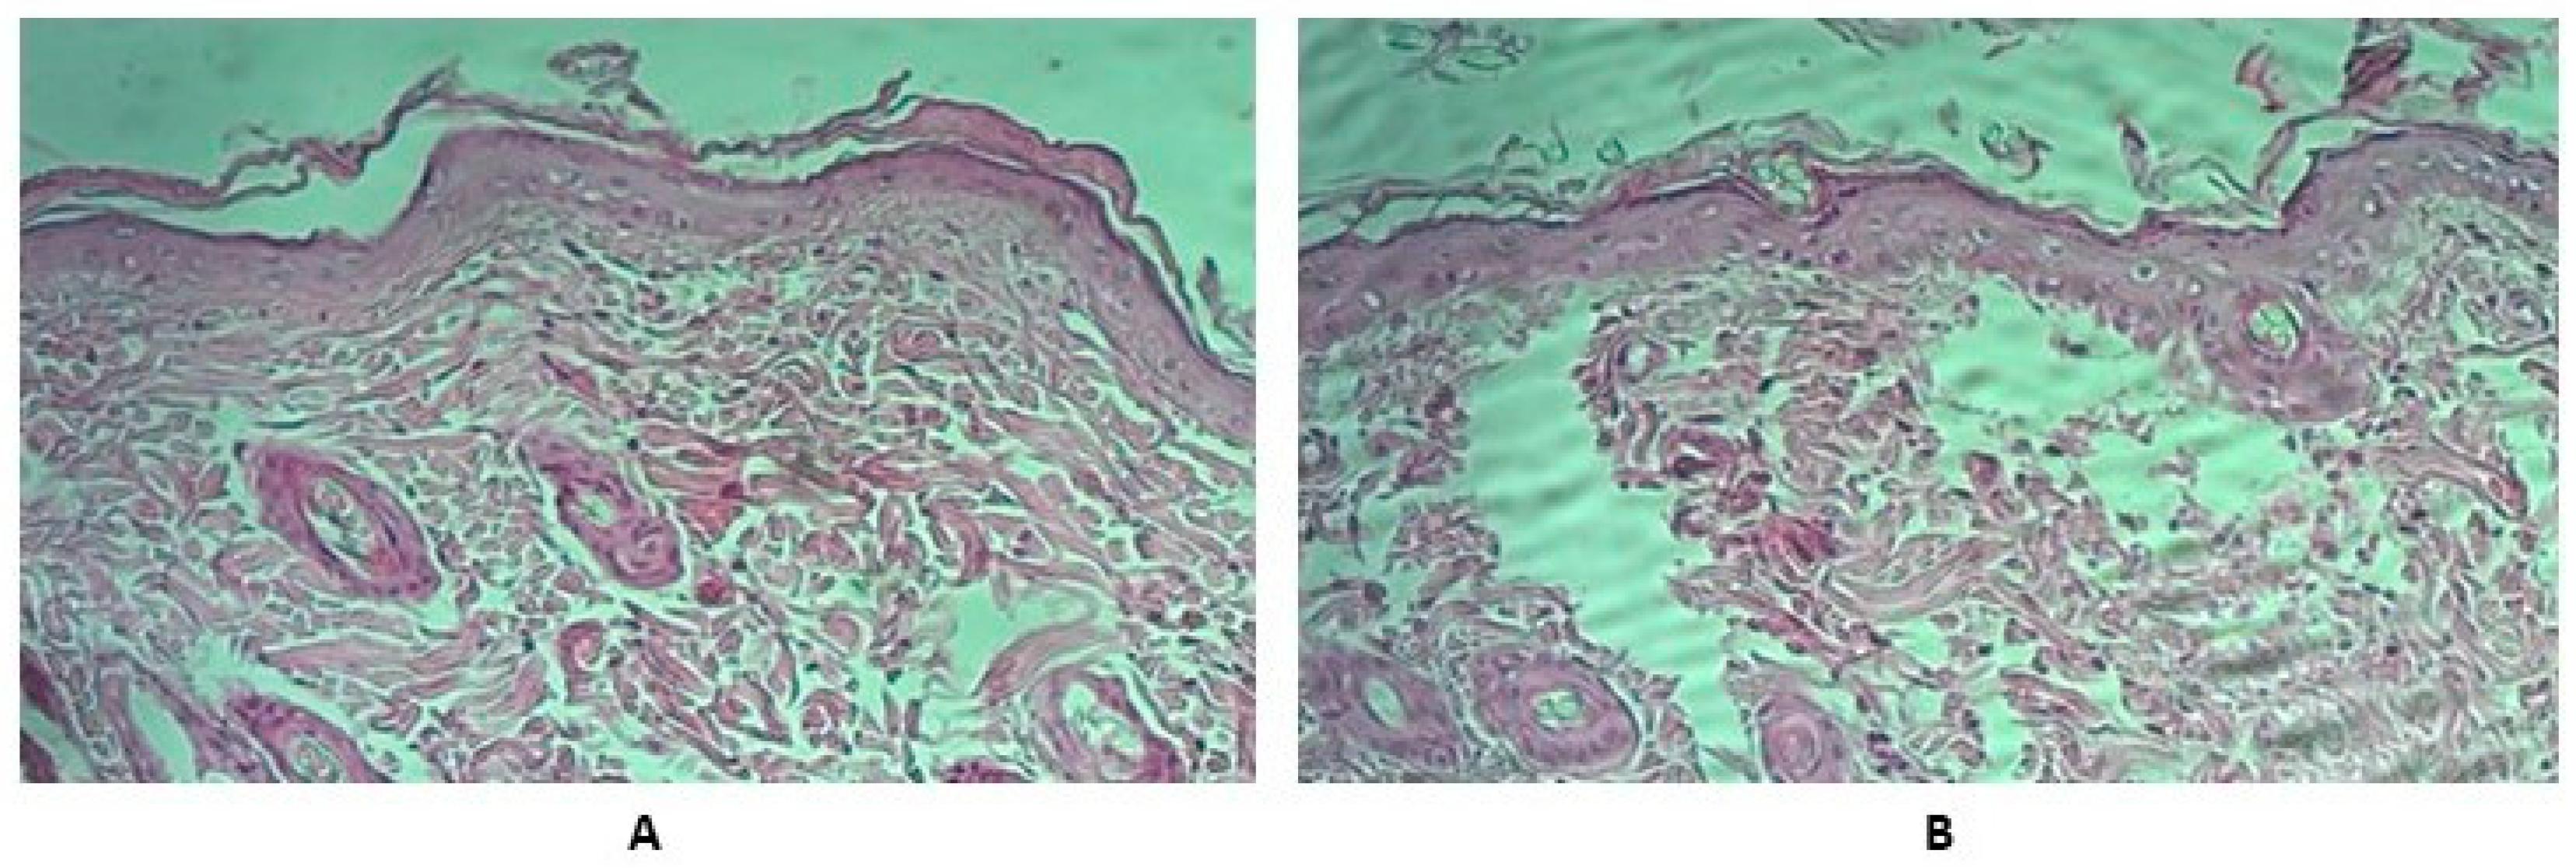

We noted no changes at the animals’ injection site or any pronounced pathological changes such as hyperemia, swelling, erythema, peeling, infiltration, irritation, or tissue necrosis after administering the vaccine. The animals’ skin at the injection site was normal, with no signs of irritation. At the end of the experiment, we decapitated all animals to assess the macro- and microscopic skin changes. This examination found that the skin and subcutaneous tissue at the injection site were unchanged. There were no hemorrhages, infiltration, irritation, or tissue necroses observed.

We performed a pathomorphological examination of rats’ skin and tissues adjacent to the injection site. We fixed the collected skin samples in a 10% formalin solution and stained ready sections with hematoxylin and eosin. Microscopy of skin samples from control group animals showed that the skin preserved its histological structure and had only small dermal edema foci (Figure 3).

Figure 3. Typical results of samples’ pathological examination (HE × 200). Hematoxylin and eosin staining. (A) Control group skin sample. (B) Experimental group skin sample. We shaved an area of approximately 5 cm2 around the injection site of each animal 24 h before the experiment. We tried to avoid injuring the animals’ skin in the procedure. We administered the vaccine undiluted in the amount of 0.5 mL by injecting it at the site we had prepared. Thereafter, we observed the skin for 12 h.